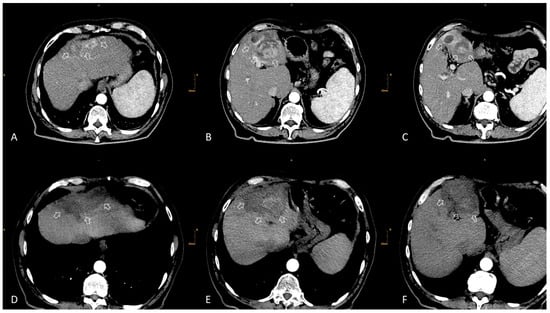

3. TACE

3.1. Eastern Perspective

3.2. Western Perspective